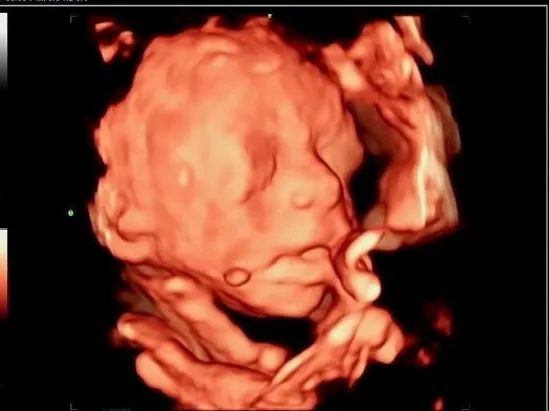

面横裂

孕妇 XXX 女 28 岁 G1PO 孕 25W1D

在我院行四维超声时发现右耳及右侧面颊部见赘生物,右侧口角增大,考虑面横裂。跟家属告知情况后孕妇继续妊娠至足月娩出一女婴,Apgar 评分:10 分,生后右侧可见附耳,右侧口角增大,其旁见赘生物,证实了产前的面横裂的诊断。

面横裂又称为巨口症,是由于第一鳃弓上颌突及下颌突融合异常所致面横裂可为单侧裂,表现为两侧口角不对称;也可为双侧裂。除口颊畸形外,还可伴第一腮弓的发育畸形,如颜面部一侧发育不良、耳前瘘管以及附耳等畸形。发生率在 1/3000~1/5000。

产前超声诊断面横裂非常困难,特别是Ⅰ级面横裂更难发现,大多数病例都是生后发现。单纯面横裂可以在孩子三个月以后通过手术治愈,预后佳。